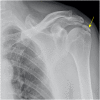

The rotator cuff is a group of four muscles and tendons surrounding the shoulder joint providing it strength and stability. The rotator cuff consists of the subscapularis, supraspinatus, infraspinatus and teres minor. Many shoulder complaints are caused by rotator cuff pathology such as impingement syndrome, tendon tears and other diseases e.g. calcific tendonitis. Diagnosis starts with clinical history and physical examination, after which imaging is often used to help confirm clinical findings depending on the differential diagnosis. The aim of the article is to review the frequently used imaging modalities to assess the rotator cuff and cuff-related disease, specifically focusing on radiography, ultrasonography and magnetic resonance imaging. This article will outline the advantages and disadvantages for each modality and illustrate typical radiological findings of common rotator cuff pathologies.